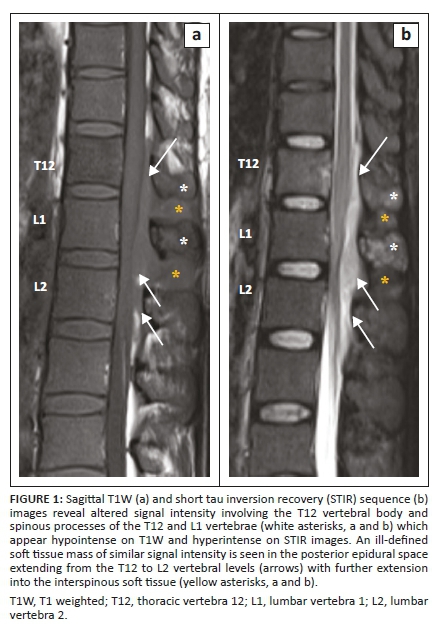

The MRI examination revealed altered signal intensity involving the bodies and posterior elements of the T12 vertebra and L1 vertebra which showed hypointense signal on T1 weighted (T1W) and hyperintense signal on T2W and short tau inversion recovery (STIR) sequences (Figures 1 and 2) with mild enhancement on post contrast images. On chemical shift imaging, the involved vertebral body did not show reduction in signal on opposed phase images (Figure 3). There was a homogeneously enhancing soft tissue mass in the posterior epidural space extending from the T12 to L2 vertebral levels appearing isointense on T1W and hyperintense on T2W and STIR images (Figures 2 and 4). The lesion caused narrowing of the spinal canal with marked compression of the conus medullaris and cauda equina nerve roots. There was associated widening of bilateral neural foramina (right > left) at the T12-L1 and L1-L2 levels, with infiltration of the soft tissue lesion into bilateral paraspinal muscles. A possibility of myeloid sarcoma was suggested given the clinical profile and imaging findings.

A precise and prompt diagnosis of chloroma is crucial as it allows the institution of definitive radiotherapy or adjuvant chemotherapy for local control of the disease, which helps in relieving cord compression and obviates any unnecessary surgery. Magnetic resonance imaging forms the cornerstone in the evaluation and diagnosis of spinal involvement in chloroma by aiding in spatial localisation (i.e. vertebral, epidural, intradural extramedullary and intramedullary), determining its extent and assessing the degree of cord compression, if present. At MRI, vertebral involvement in chloroma manifests as focal, multifocal or diffuse leukaemic infiltration of the vertebral marrow with low signal intensity on T1W, high signal intensity on T2W images and avid enhancement on post contrast images. Chemical shift imaging remains a useful entity when differentiating this condition from red marrow conversion. A propensity for ligamentous and subperiosteal involvement is also seen as a result of spread via the haversian canals.6 However, this non-specific appearance can be confused with marrow infiltrating disorders such as multiple myeloma and lymphoma; hence, a thorough clinical history of haematological disease is imperative in establishing the diagnosis.

Epidural involvement in chloroma can often occur in conjunction with vertebral body involvement. These often present as multiple masses which may be either contiguous or discrete, involving different vertebral levels. They usually show isointense and intermediate signal on T1W and T2W images respectively, with homogeneous post contrast enhancement.7,8 Central non-enhancing necrotic areas may be identified and diffusion restriction may be noted on diffusion weighted images. The lesions can cause effacement of the epidural fat with inward displacement of the dura mater and compression of the spinal cord with partial or complete obliteration of the cerebrospinal fluid (CSF) space. Frequent association with compressive myelopathy or neuronopathy, regardless of lesion location, is also seen. The combined intra-extraspinal form of chloroma, with a resultant 'dumb bell configuration', may simulate the appearance of a nerve sheath tumour on imaging. In such scenarios, absence of intense T2 hyperintensity without secondary bony changes (destruction or remodelling) favours chloroma.4